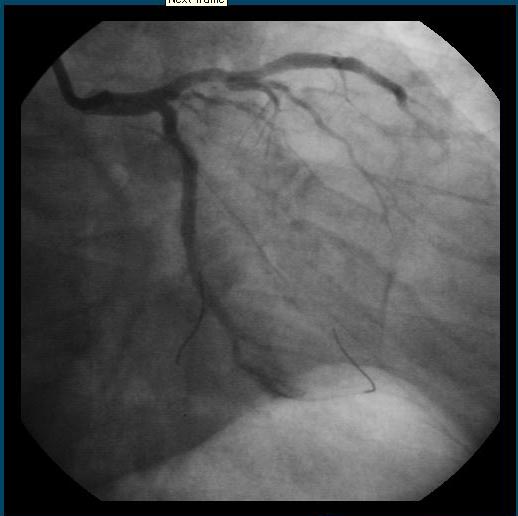

病院勤めの経験からこの病院のすばらしさはある程度しっていましたから、手術室のオペ台に乗ってからも周囲をながめて素晴らしい設備だなあーと思いながら時計を見るとほぼ12時でした。Cアーム透視モニターの画面が、もっと見えないかなとも思いながら、下腹部で何やら手術の準備をしているなあぐらいにしか考えていませんでした。その後の状態は何も覚えていません

やがて、再びドクターの「胸が、熱くなりますよー」と言う声とともに左の鎖骨の付近から腰に向かってビー玉位の大きさの熱い固まりが体の中を下がって行くのを感じるととも楽になりました。しばらくして、右の太ももの付け根のお腹に強烈な圧迫が加わり、ドクターが、全体重をかけて押さえていました。(動脈からのカテーテル手術なので当然なのですが)そして、数キロの重さはあろうかと思える砂袋に代えられました。そして、右足は、「よしと言うまで絶対に動かさないで!!」と言われ拘束(縛られた)されました。